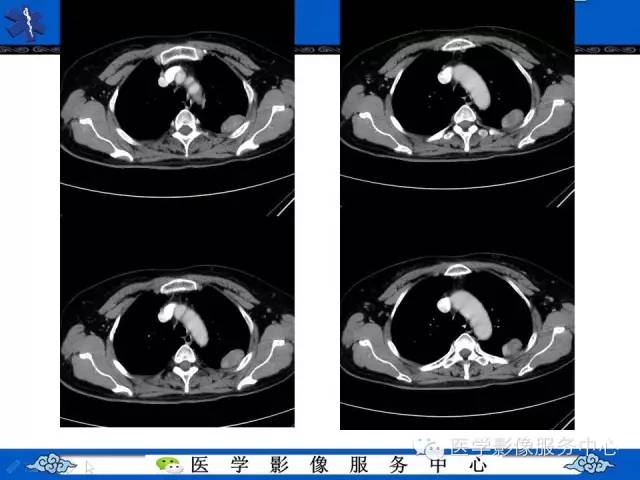

胸膜孤立性纤维瘤1例CT影像表现与鉴别

【病例】胸膜孤立性纤维瘤1例CT影像表现与鉴别